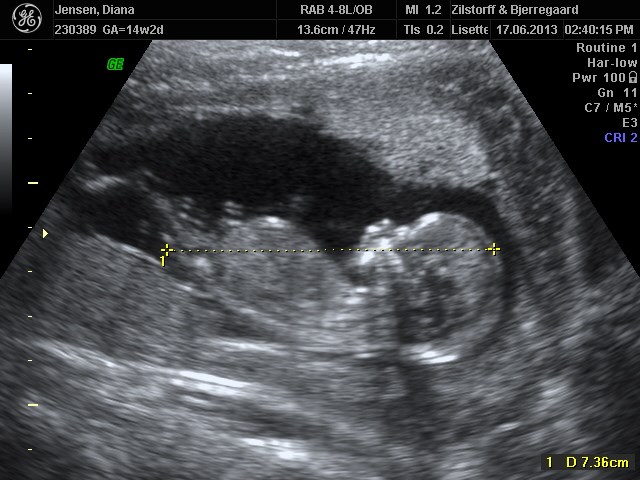

og self. kommer der lidt billeder

tvilling 1 først og tvillinge 2 næste og samme med mål